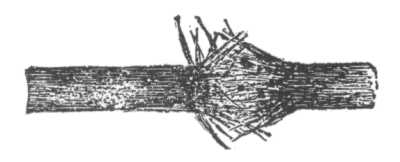

Fig. 8.

Demodex Folliculorum, X 300. Ventral surface. (After Simon).

To what may comedo often be ascribed?

To disorders of digestion, constipation, chlorosis, menstrual disturbance, lack of tone in the muscular fibres of the skin, the infrequent use of soap, and working in a dirty or dusty atmosphere. [Pg 40] A small parasite (demodex folliculorum, acarus folliculorum) is sometimes found in the sebaceous mass, but its presence is without etiological significance, as it is also found in healthy follicles. A microbacillus has been found by several observers, and credited with etiological influence.